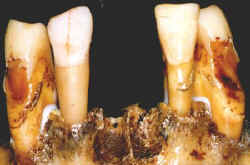

Destruição óssea alveolar causada por periodontite crônica.

espaco2.gif (821 bytes)Os centrais podem ter sido perdidos após a morte.